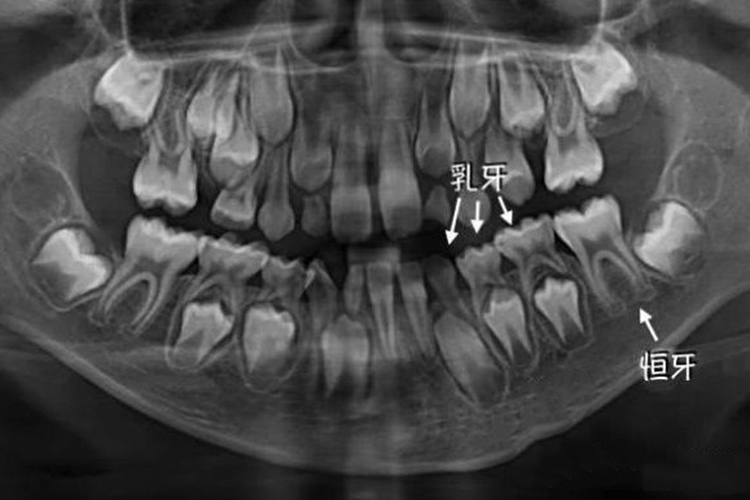

正常情况下儿童出生时乳牙已骨化,乳牙牙孢隐藏在颌骨中,被牙龈覆盖,出生后4-10个月开始萌出。6岁左右恒牙萌出,乳牙逐渐被替换。牙片可见乳牙牙列下方有恒牙存在,牙齿外层有发白透亮度较高的牙外形,中间有1-2条根状直线阴影。